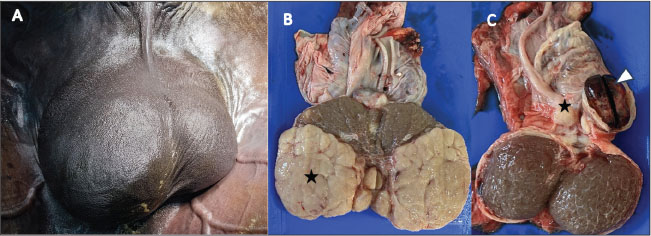

Fig. 1. Marked scrotal asymmetry in an adult stallion, characterized by a pronounced enlargement of the right testicle (A). Post-castration gross examination shows multiple lobulated masses of variable size and beige to dark beige color occupying most of the right testicular parenchyma (B) (asterisks), with whitish fibrous areas visible at the center of the section (white arrows). A well-demarcated hemorrhagic lesion is observed cranially to the left testis at the level of the epididymal head (C) (arrowhead), consistent with a localized hematoma, with an adjacent nodular lesion (asterisk).

Post-castration examination of the right testis showed multiple firm, lobulated masses of varying sizes, occupying approximately the caudal two-thirds of the parenchyma (Fig. 1B). The combined diameter of the masses was approximately 14 cm. The remaining parenchyma contained scattered pale, irregular areas interspersed with zones that appeared relatively preserved (Fig. 1B).

On the left side, a small, well-circumscribed 3-cm nodule was found above the left testis, along with a localized hematoma at the epididymal head. The cut surface of the neoplastic tissue was beige to dark beige in color and firm in texture, while the hemorrhagic area appeared dark red-brown, with partly clotted blood and mild compression of the adjacent parenchyma (Fig. 1C).

These observations confirmed bilateral involvement, with lobulated neoplastic tissue in the right testis and a peri-epididymal nodule with focal hemorrhage on the left (Fig. 1B and C).